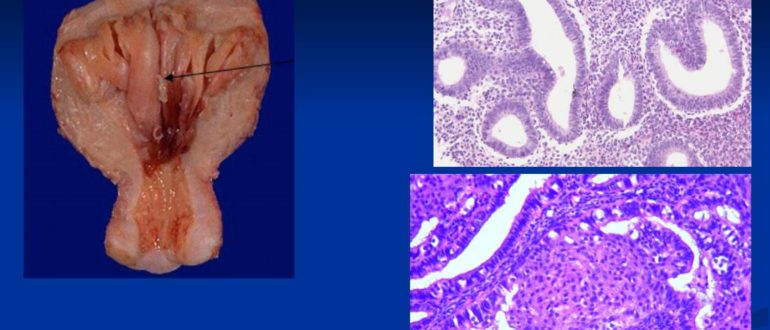

Все о ЖГЭ — железистой гиперплазии эндометрия Железистая гиперплазия эндометрия – серьезное заболевание, встречающееся у молодых и зрелых женщин. Существует несколько форм заболевания, при некоторых возможно предраковое состояние….